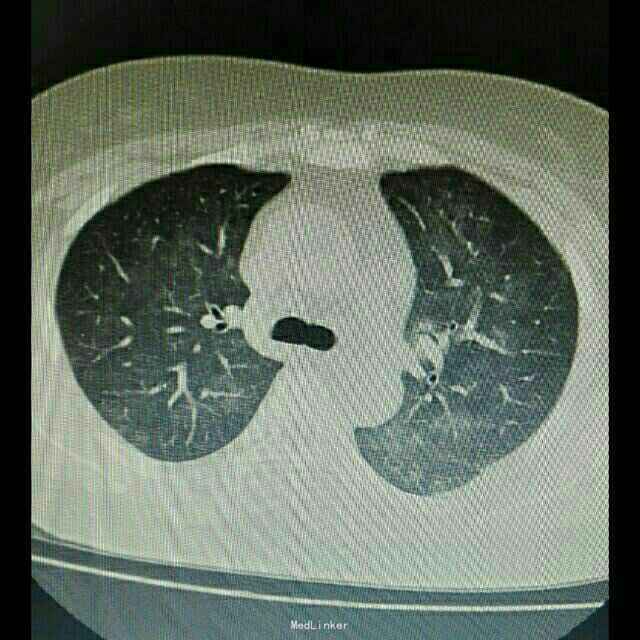

辅助检查:入院后行紧急胸部CT检查提示双肺弥漫性炎症改变,双下肺更加明显。

诊断:肺部感染,异体肾移植状态 治疗:根据胸部CT检查提示,真菌感染可能性大,给予科赛斯抗真菌治疗,加用舒普深抗细菌治疗。进一步检查生化、降钙素原、真菌D葡聚糖等炎性指标,监测患者体温、血气等指标。